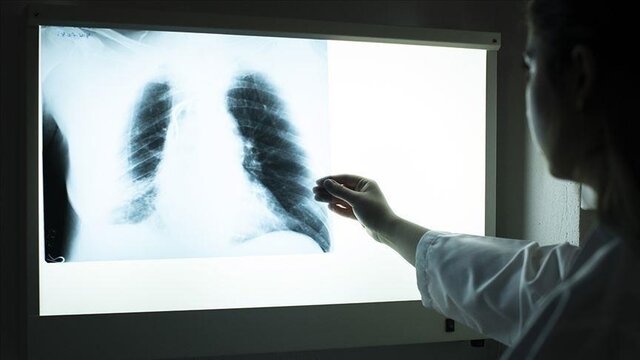

سل، یک بیماری عفونی شایع و در بسیاری از موارد مرگبار است که توسط مایکوباکتریوم توبرکلوزیس ایجاد میشود. علائم کلاسیک این بیماری شامل سرفه مزمن با خلط خونی، تب، تعریق شبانه و کاهش وزن است. این بیماری عمدتاً به ششها حمله میکند، اما میتواند بر قسمتهای دیگر بدن نیز تأثیر بگذارد. عفونتهای سل بهطور معمول از طریق هوا منتقل میشوند و اغلب عفونتها بدون علامت و پنهان هستند، اما معمولاً از هر ۱۰ عفونت نهفته، یک مورد به بیماری فعال تبدیل میشود.